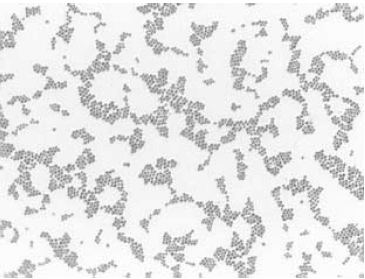

A figura abaixo é compatível com a morfologia do microrganismo identificado na secreção.

Material recebido em laboratório para análise microbiológica por bacterioscopia, cultura e antibiograma revelou a presença de Staphylococcus sp. O material é proveniente de swab coletado de ferida cirúrgica que apresenta resposta inflamatória intensa e secreção purulenta. Como o objetivo do médico era identificar o foco infeccioso, e havia suspeita de infecção urinária, também foram solicitados EAS e urocultura.